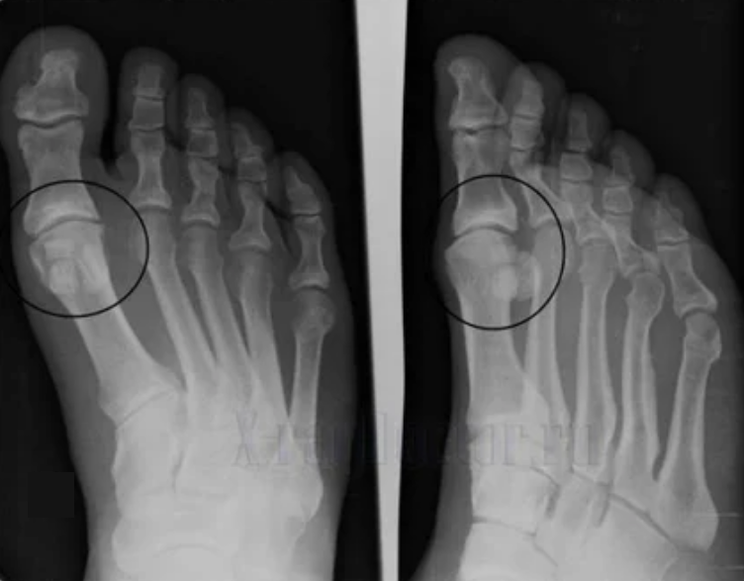

To diagnose, rheumatologists study the patient's complaints and prescribe an X -ray examination.Most often, radiography is used in 2 projections.The doctor considers the presence of dystrophic disorders in hyaline cartilage and bone joints.If the joint is reduced, the bones are deformed or flattened, there are cystic formations on the surface of the cartilage, osteophytes are obvious signs of arthrosis.During the inspection, arthrosis shows the instability of the joint: the axis of the limbs and subluxation is disturbed.

Often an X -ray picture is not able to provide complete information about the condition of the joint.Computed tomography is prescribed for a more in -depth study, it is effective for bone examination.MRI is used more frequently to examine soft tissues.